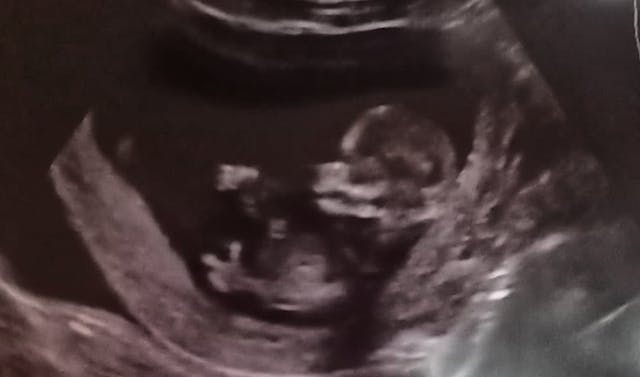

When I was pregnant, I had a vague feeling something was off: at 10 weeks I started bleeding and I thought I was having a miscarriage. But after a week the bleeding stopped, there was a heartbeat the whole time, and we saw our little man spinning around in my tummy and making finger guns.